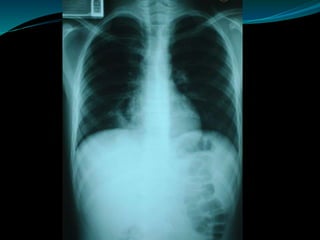

 La radiografía de tórax va a

mostrar una masa sólida,

multiquística o quística,

frecuentemente

posteromedial y en los

lóbulos inferiores.

 Densidad más uniforme,

puede ser oval, fusiforme,

generalmente basal a

izquierda.

DIAGNÓSTICO INTRALOBAR EXTRALOBAR  Laradiografía de tórax va a mostrar una masa sólida, multiquística o quística, frecuentemente posteromedial y en los lóbulos inferiores.  Densidad más uniforme, puede ser oval, fusiforme, generalmente basal a izquierda.